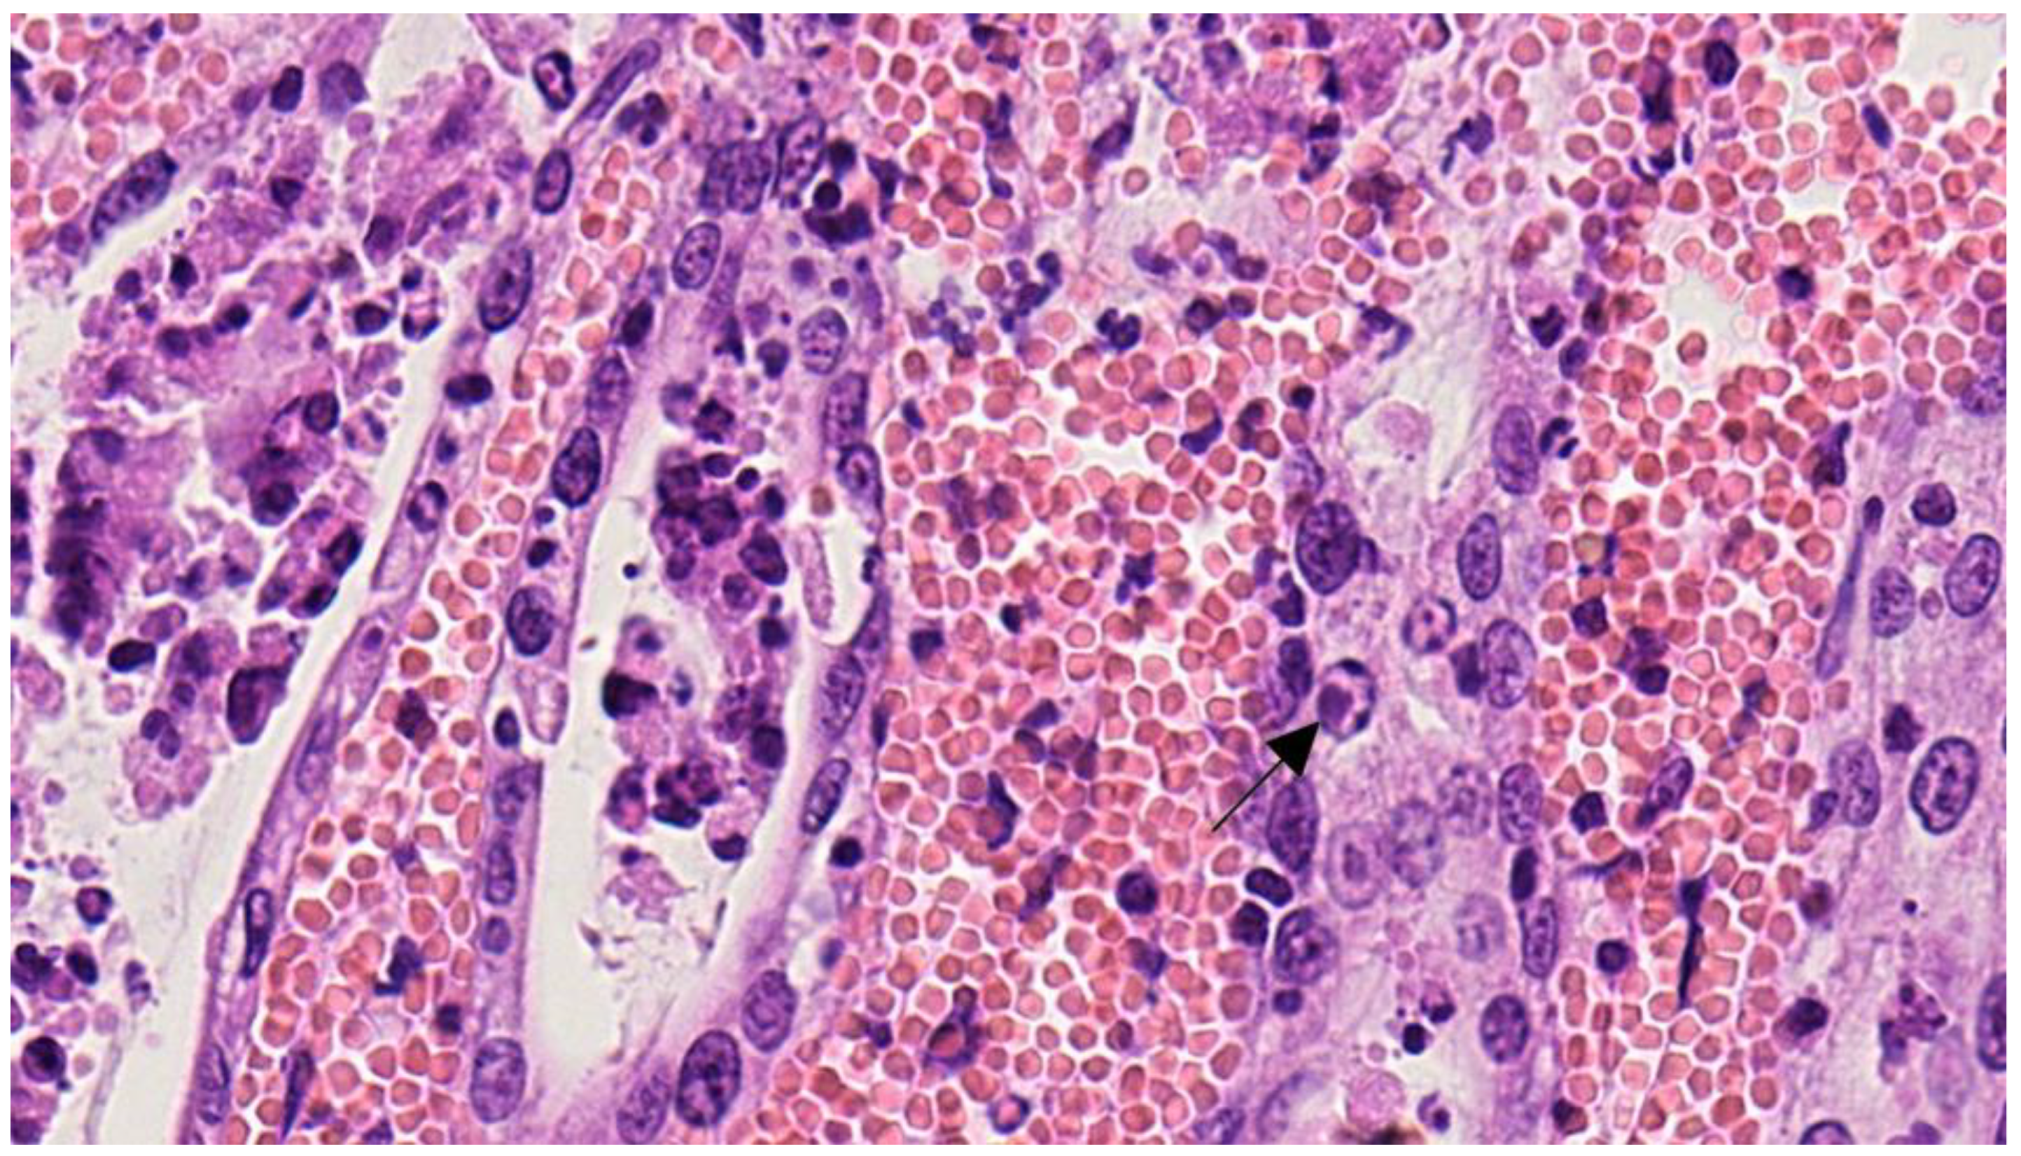

2.1. Anatomopathological Examination